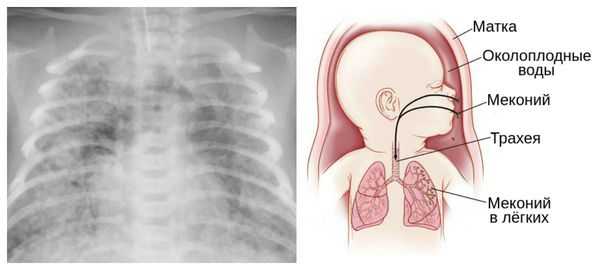

Осложнения перенашивания беременности

Для плода большую опасность представляет асфиксия (острая гипоксия) и отслойка плаценты. Нехватка кислорода внутри утробы стимулирует плод выполнить несвоевременные дыхательных движения. Они приводят к заглатыванию вод и возможному воспалению лёгочной ткани — пневмониту. Если в водах есть примесь мекония (первородного кала), то велика вероятность мекониальной аспирации — проникновения содержимого кишечника новорождённого в его лёгкие.

Опасности переношенной беременности для ребенка заключаются в возможной гипоксии плода и асфиксии новорожденного, развитии поражений головного мозга, получении родовых травм, аспирации мекония и околоплодных вод. Состояние детей, родившихся от переношенной беременности, отягощается выраженной желтухой, гормональными кризами, инфекционными поражениями кожи, неврологическими нарушениями. Впоследствии они нередко отстают от нормального физического и психического развития.

Из-за снижения кровотока в почках плода выделение мочи значительно уменьшается, развивается маловодие. Также изменяется характер околоплодных вод: они теряют прозрачность, становятся мутными, приобретают желтоватый или зеленоватый оттенок из-за примеси мекония — первых фекалий ребёнка.